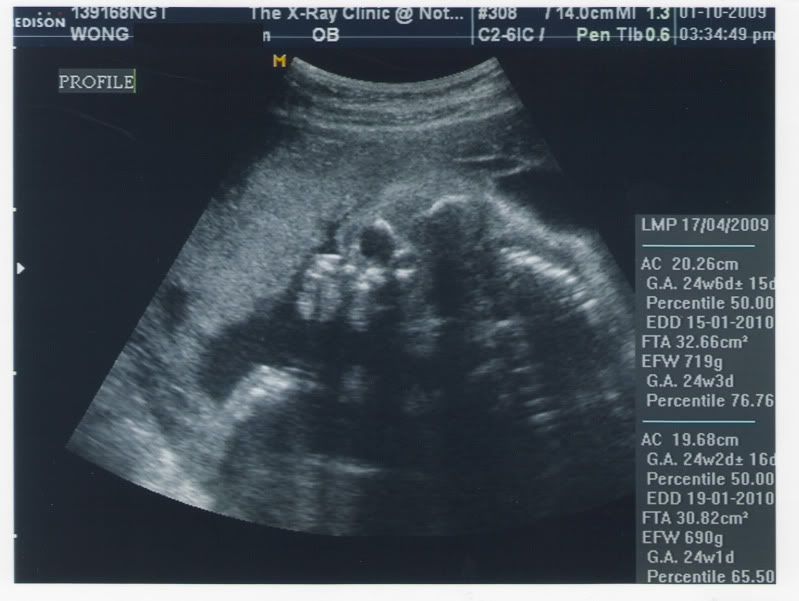

今天照完 ultrasound~

可是睇唔明 D data....

this is one of the photos I PAID for:

我睇唔明係上面 or 下面既 data 係我牛 B既 measurement....

為什麼有2組數, 而圖片真是不知是什麼部分! 我沒圖片在公司, 不過今晚去私家覆診, 到時可以再和您compare一下!

我懷疑上同下都係妳個B既data,

只不過分開兩次度既時候, 數字有偏差,

以致連預計生產日期都有4日既差別~